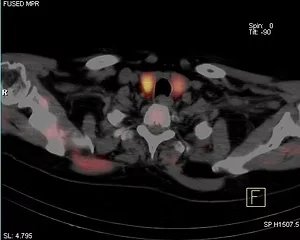

Parathyroid Scan

A parathyroid scan is performed to detect and localize parathyroid adenomas.